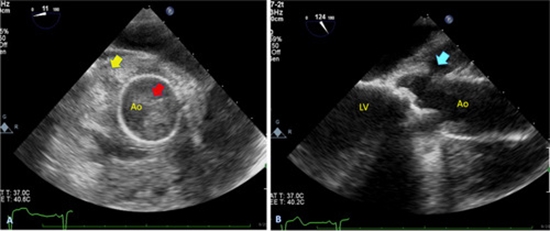

Case presentation: This report details a case of extensive ascending aorta involvement in Aspergillus endocarditis (AE) in a 24-year-old man with a history of bioprosthesis aortic valve replacement (AVR). Three months post-AVR, he presented with pericardial effusion and aortic rupture, leading to a redo biological valved conduit aortic root replacement (Bentall surgery). Despite the intervention, the tubular graft exhibited extensive Aspergillus involvement, resulting in graft disruption and significant peri-aortic infection. A second redo procedure involving aortic homograft root replacement was performed. Unfortunately, the patient succumbed two days after the surgery.